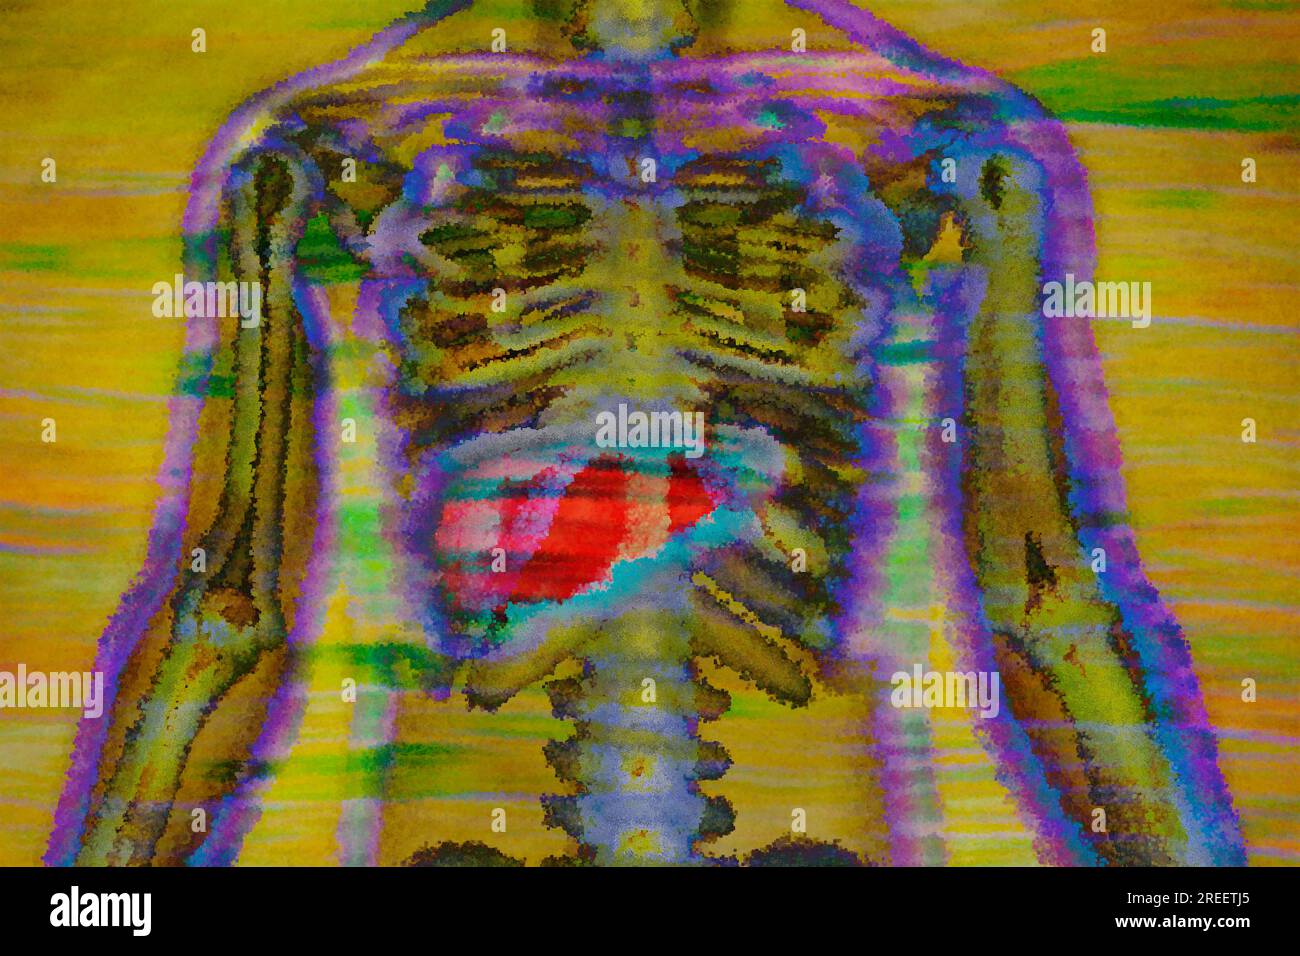

RF2RW4YD3–Le foie est l'un des plus grands organes du corps avec de nombreuses fonctions importantes pour le métabolisme. Il convertit les nutriments de la nourriture en substances qui

RF2REETK6–La glande thyroïde est située dans le cou et a de nombreuses tâches dans les domaines du métabolisme, des hormones et de la croissance

RF2REETJ7–La glande thyroïde est située dans le cou et a de nombreuses tâches dans les domaines du métabolisme, des hormones et de la croissance